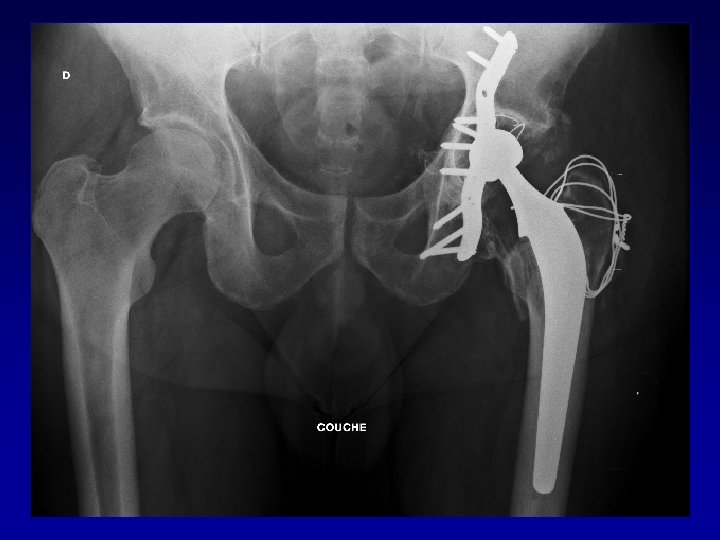

Arthroplastie totale de hanche sur fracture du cotyle complexe Recentrage, reconstruction, orientation du cotyle • • Greffe Ostéosynthèse par plaque MK Surtout si pseudarthrose Réduction de la luxation

Bilan • • Type de fracture du cotyle Déformation de la cavité cotyloïdienne Chirurgie préalable Raideur Ostéome Nécrose de la tête fémorale Luxation invétérée

Déformation du cotyle • Ascensionné • Perte de substance osseuse scanner • Pseudarthrose • Perte du positionnement exact (idem LCH) • Doit être reconstruit et recentré